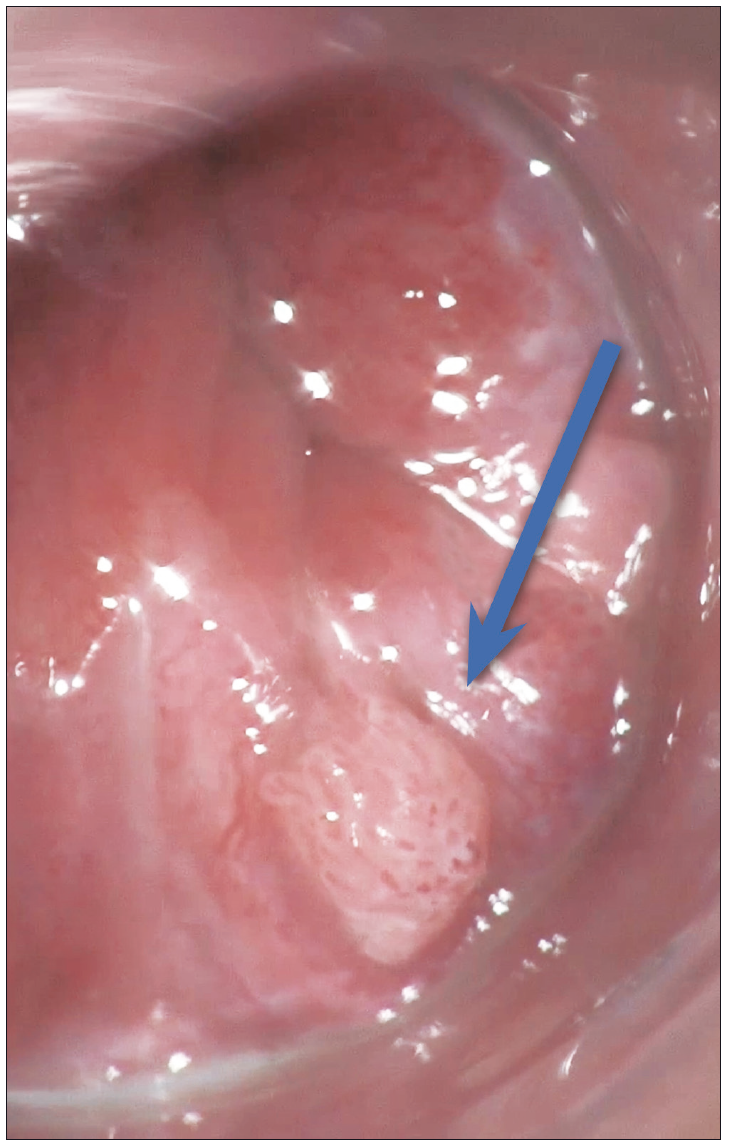

Otra lesión tumoral no dolorosa la constituye la presencia de verrugas genitales (condilomas) producidas por el VPH (virus del papiloma humano). Pueden ser pequeñas o grandes y confluyentes, con un aspecto coliforme de coloración blanquecina. (Figura 2) En estos pacientes es conveniente la investigación de otras enfermedades de transmisión sexual. El estudio con anoscopia de alta resolución facilita la detección de lesiones de alto grado preneoplásicas.4 (Figura 3) El tratamiento de las lesiones del VPH es esencial para prevenir el contagio, la extensión de las lesiones por autoinoculación y la progresión a neoplasias. En este artículo se describen tratamientos tópicos, ablativos y resectivos, como por ejemplo topicación con ácido tricloroacético, imiquimod, electrofulguración, láser o resección quirúrgica.4

Figura 3. Anoscopia de alta resolución 20X. Lesión condilomatosa endoanal de bajo

grado sobre la línea pectínea (flecha)